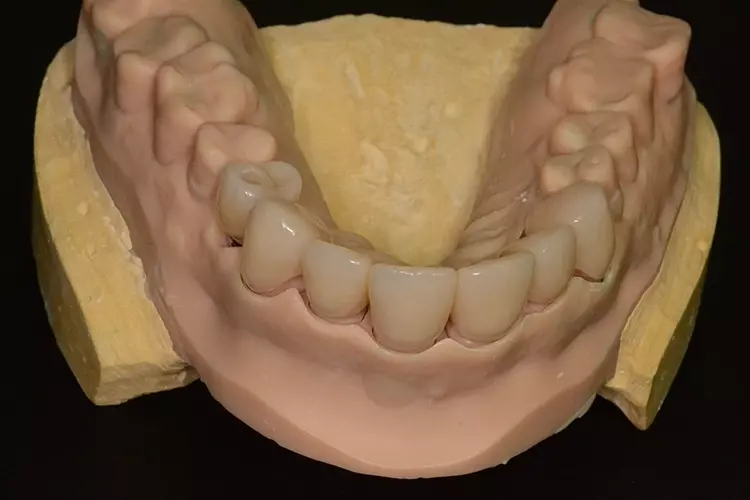

Neuversorgung Oberkieferfront auf Altimplantat 21

Die 49-jährige Patientin beklagte die ungleiche Höhe der Schneidekanten an den Kronen 11 und 21. In diesem Zusammenhang wurde das Gesamterscheinungsbild analysiert und entschieden, die Zähne 13-23 zu überkronen und dabei die Altkronen an 11 und an dem Implantat 21 zu erneuern. Die verschachtelt stehenden Zähne im Unterkiefer sollen im Nachgang per Aligner-Therapie ausgerichtet werden.

Dabei wurde die beabsichtigte Situation im Vorab per Wax-up simuliert. Beim Entfernen der Altkrone 21 wurde ersichtlich, dass ein Titanabutment eingesetzt wurde, an dem sich Konkremente und Zementreste befanden, die zu einer marginalen Mukositis am Implantat führten.